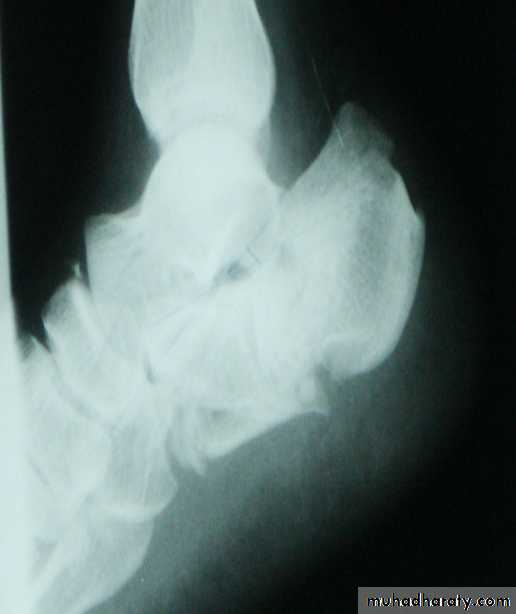

In cancellous bone trauma produce comminuted crush fracture.

Around joint pulling ligament and tendon produce avulsion fracture.How fracture are displaced: